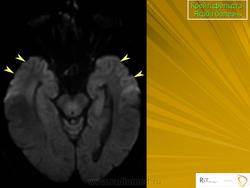

(а) MPT, FLAIR, аксиальный срез: определяется асимметричное повышение интенсивности сигнала от головок хвостатых ядер, больше слева, и левой скорлупы.

(б) МРТ, ДВИ, аксиальный срез: у того же пациента через несколько недель отмечается асимметричное повышение интенсивности сигнала от базальных ганглиев, больше слева, и от коры больших полушарий. При БКЯ более часто наблюдается асимметричное вовлечение в процесс коры, чем базальных ганглиев. У этого пожилого мужчины наблюдалась быстро прогрессирующая деменция и был поставлен диагноз вероятная БКЯ, так как при ЭЭГ были выявлены характерные признаки.